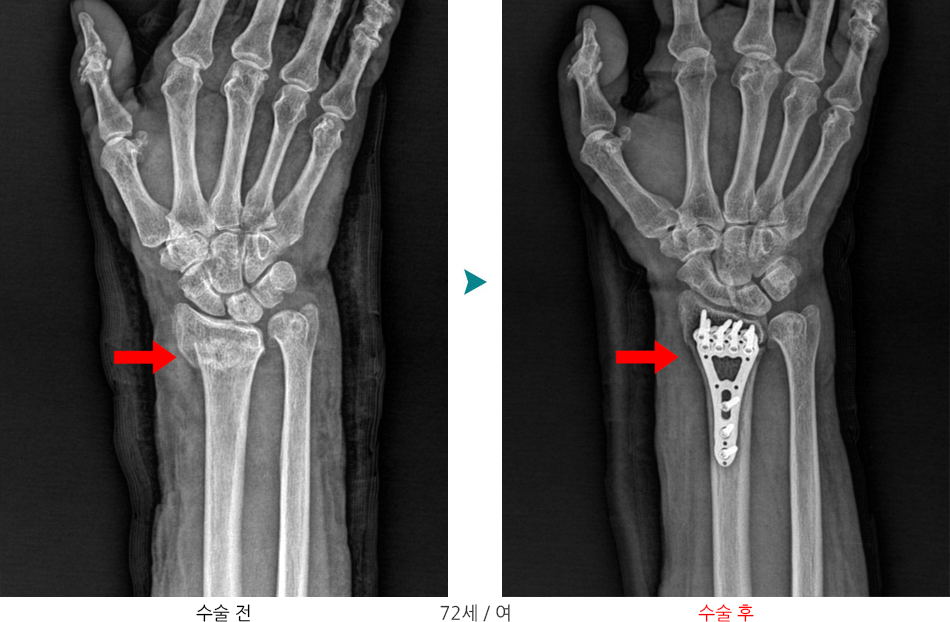

요골하단 골절은 손목(요골의 먼쪽 끝부분)에 발생하는 골절을 말합니다.

즉, 전완뼈(요골)의 끝이 부러져 손목 관절 부위의 정렬이 흐트러진 상태입니다.

심한 변위 또는 정복 유지가 불가능한 경우

- 개방적 정복술 및 금속판/금속나사를 이용한 내고정술 시행